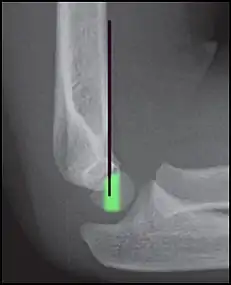

Anterior humeral line - It is a line drawn down along the front of the humerus on the lateral view and it should pass through the middle third of the capitulum of the humerus.[9] If it passes through the anterior third of the capitulum, it indicates the posterior displacement of distal fragment.[8]

Anterior humeral line (black line), with normal area passed on the capitulum of the humerus colored in green in a 4 year old child.[9]